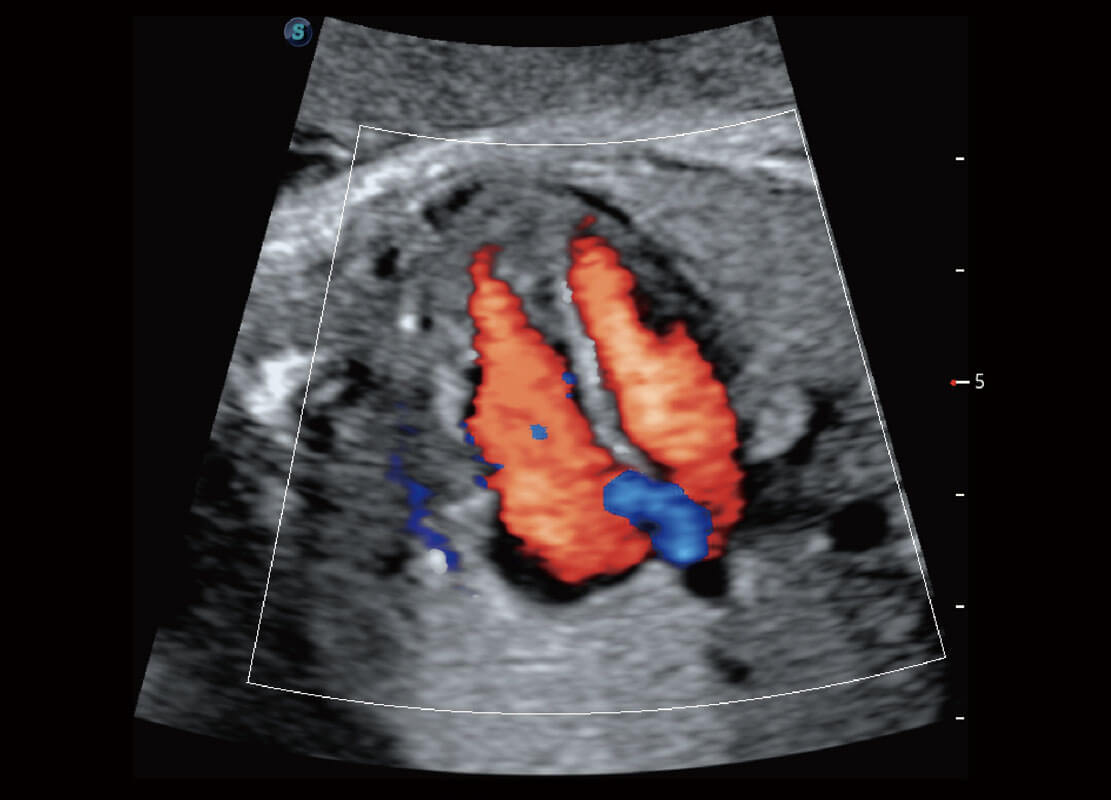

P60搭载一系列胎儿心脏成像技术,实现精细的胎儿心脏评估。

四腔心血流

右室双出口

胎心容积成像